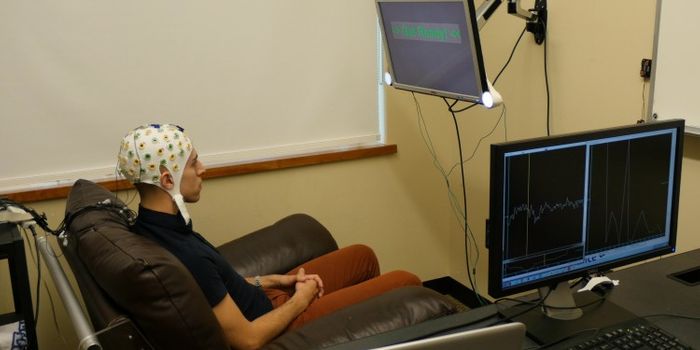

MAY 18, 2016NeuroscienceCan you move things with your thoughts? As it turns out, some people can, but they are not carnival performers or nightc ...

JUL 13, 2015NeuroscienceA group of scientists from various organizations has come together to help people to communicate, bringing together neur ...